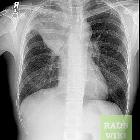

Plain radiograph / CT

The imaging features of atelectasis are similar on plain radiographs and CT with more detail being available on the CT:

- increased density at the site of atelectasis

- loss of normal thoracic silhouettes

- displacement of the fissures toward the area of atelectasis

- upward displacement of ipsilateral hemidiaphragm

- crowding of pulmonary vessels and bronchi affected area

- compensatory hyperinflation of the unaffected lung

- mediastinal shift

- ipsilateral tracheal deviation

- ipsilateral shift of the heart